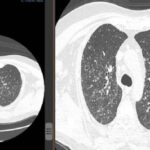

En la tomografía computada de tórax en ventana pulmonar se identifica un patrón micronodular con distribución perilinfática y difusa en ambos hemitórax. Este hallazgo se acompaña de un engrosamiento peribronquial notable, así como de opacidades en vidrio deslustrado, que predominan en las zonas subpleurales y en las regiones posteriores de ambos pulmones.